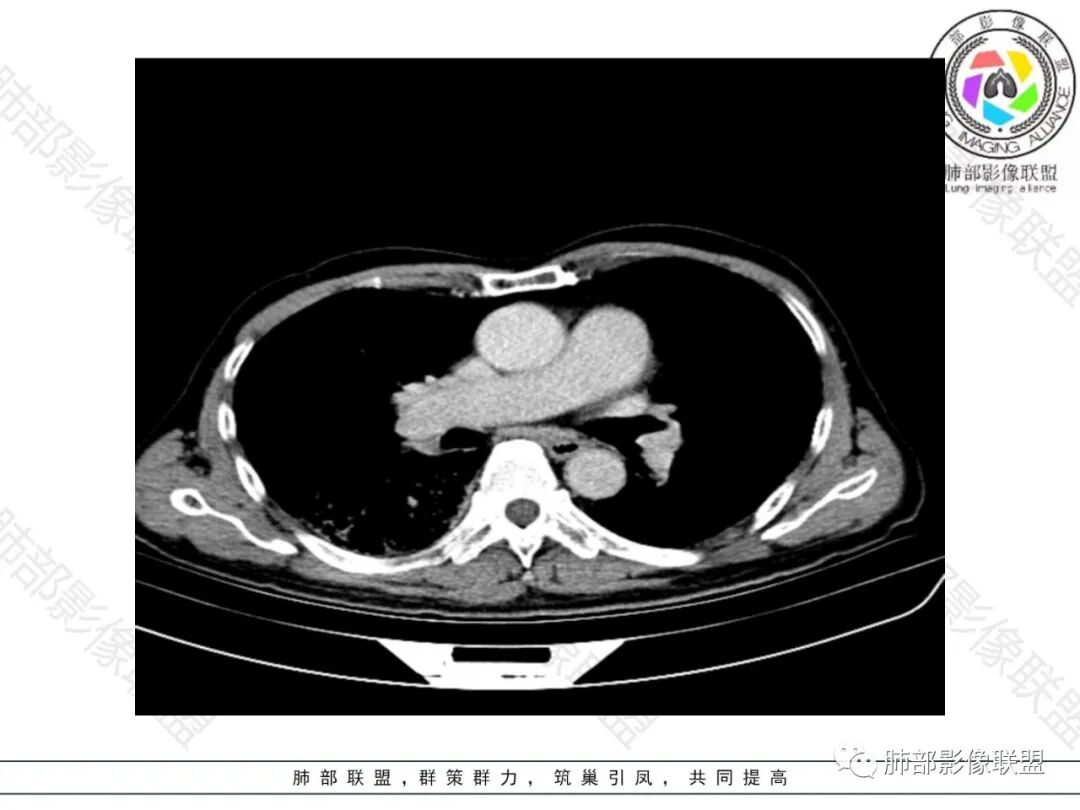

2.影像表现:肺气肿背景,右肺下叶呈现明显网格影及蜂窝影、枯枝征,边缘膨隆、叶间裂向前方推移。病灶密度不均,前份见不规则片状实性密度区,实性部分轻度强化,边界不清,周边特征掩盖不清。支气管主要分支显示,呈枯枝征。纵隔窗病灶密度偏低,病灶内血管影边缘稍显模糊,未见明显液化坏死区。

右侧肺门淋巴结肿大,中央低密度;纵隔见轻度增大淋巴结。

3.综合分析:临床方面:慢性病程、急性发作,呼吸道症状伴发热,炎性指标升高,提示存在感染可能;CA199升高,但相对特异性不高。影像双肺气肿,右肺下叶蜂窝状改变明显,夹杂实变密度区,支气管相关但未见阻塞,较常见于感染性病变,如G-杆菌感染等。蜂窝影什么时候出现我们不得而知,实变区周边特征掩盖不清。

前后三月余病灶变化不明显,右肺门异常肿大淋巴结让人警惕恶性病变可能性。

显著肺门淋巴结肿大较少出现在粘液腺癌患者,何况如此大范围病灶未见播散结节。

主要相关支气管未见明显截断,病灶内血管影较为完好,也较少见于肺鳞癌。